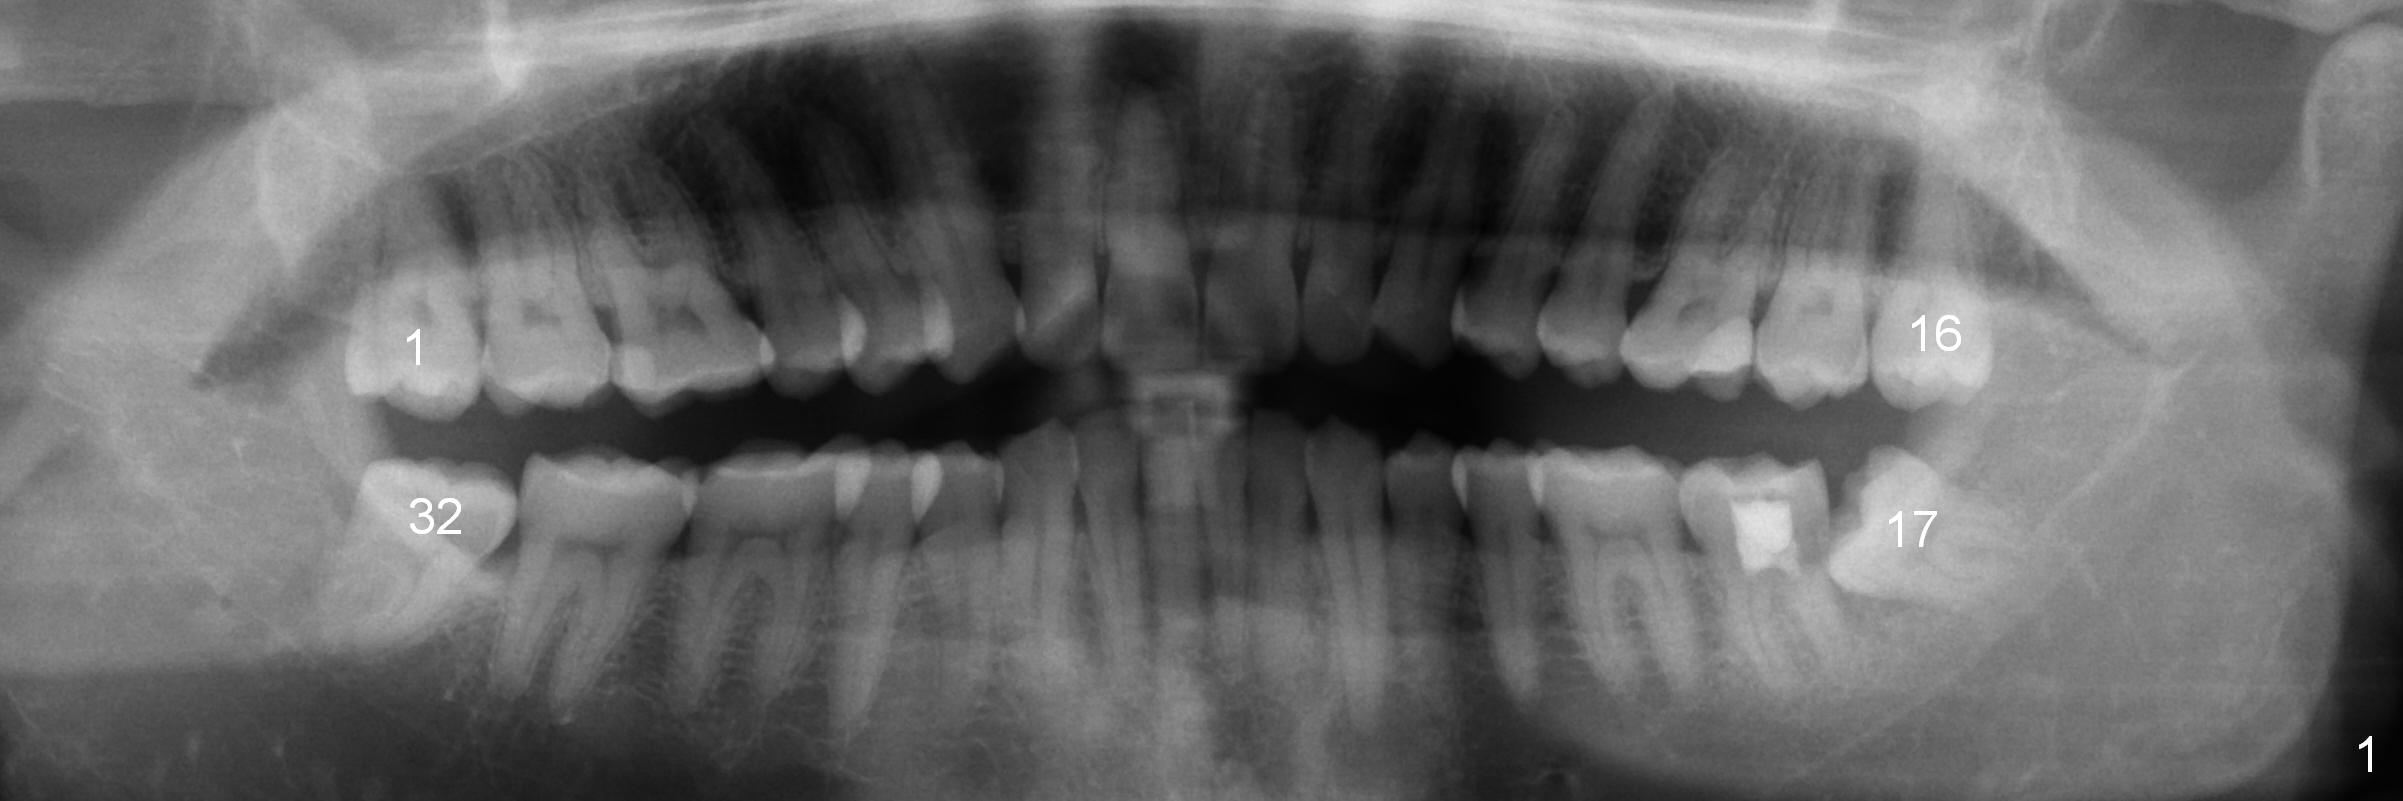

A 42-year-old man requests orthodontic treatment after extraction of the teeth #1, 16, 17, and 32, because it is easier for him to maintain oral hygiene post extraction. He thinks that orthodontic treatment will do the same. He appears to care about his dental alignment: not showing his teeth while smiling (Fig.2). The facial profile is within normal limit (Fig.3). His lower anterior teeth are moderately crowded (Fig.4) with anterior deep overbite and overjet (Fig.5,6). The deep overbite is more appreciated when the model is viewed posteriorly (Fig.7), approximately 90% of the upper incisors are covered by the lower anterior ones. More lingual surfaces are shown in another case before (Fig.8) and after (Fig.9) orthodontic treatment. With differential placement of brackets on the canines vs. incisors (Fig.6), the deep bite should be able to be corrected. Proximal reduction may be necessary.